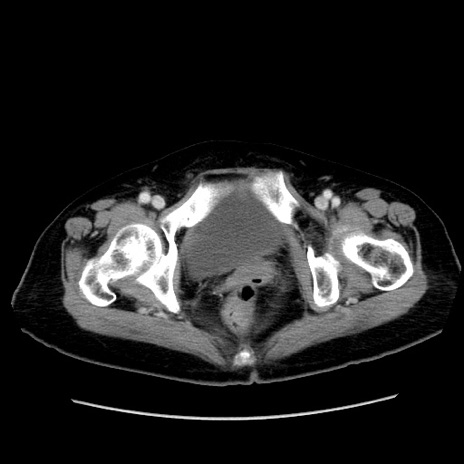

症例19(横断像)

【症例】80歳代女性

【主訴】下腹部痛

【現病歴】約8時間前より下腹部痛の出現あり、救急外来受診。

【既往歴】両側付属器切除

【身体所見】意識清明、下腹部正中に手術痕あり、その部位に一致して圧痛と反跳痛あり。腸蠕動音は亢進。

【データ】WBC 9300、CRP 0.15